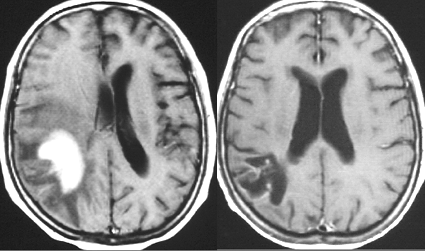

MRI検査で,はっきりわかります。MRI造影剤を入れると均一または斑らに増強(真っ白になる)されて(左側),周囲には脳の腫れ(脳浮腫)がみられます(右側)。できやすい場所は側脳室の周囲・大脳脳基底核・小脳・脳幹部など脳の深いところ(深部白質)です。脳の中に2個以上のリンパ腫が同時にできる多発例というのもしばしばあります

若い患者さんのリンパ腫です。左が診断時MRIで,黄色の矢印でみれる3ヶ所に同時にリンパ腫が発生しています。定位生検術後にすぐにMTX化学療法を3コースしたら,真ん中の画像になりました。ほとんど消失しているのですが,矢印の先にぼーっと少し残っているのでCR(消失)とはいいません。化学療法を終えた後に全脳照射30グレイをしたら右の画像になり治りました。これは順調な治療経過の例です。